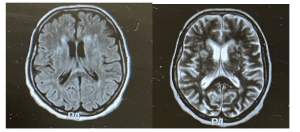

Further investigations: A repeat MRI revealed bilateral discrete periventricular and subcortical white matter hyperintensities, an electroencephalogram (EEG) showed a typical repetitive pattern of bilateral synchronous periodic epileptiform discharges, and CSF analysis via lumbar puncture revealed positive results for RT-QuIC, confirming the presence of prion protein aggregates. This led to a diagnosis of the Heidenhain variant of CJD.

Figure 2: MRI brain showing periventricular hyperintensities